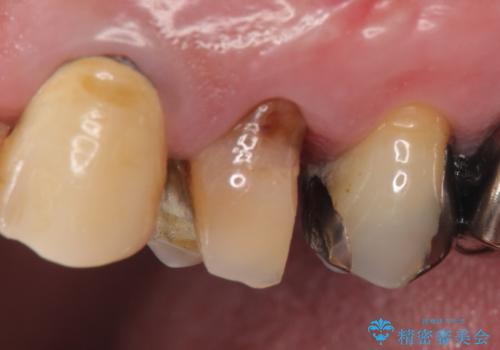

PGA(ゴールド)クラウン 脱離した銀歯の治療

- 古い銀歯が外れたので診て欲しいといらっしゃった方の症例です。

再根管治療後、PGA(ゴールド)クラウンによる補綴を行いました。

- PGA(ゴールド)クラウン…¥80,000、仮歯…¥10,000、ファイバーコア…¥20,000費用は治療当時の料金となります